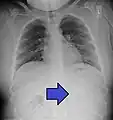

A coin seen on AP CXR in the esophagus

AP X ray showing a 9mm battery in the intestines